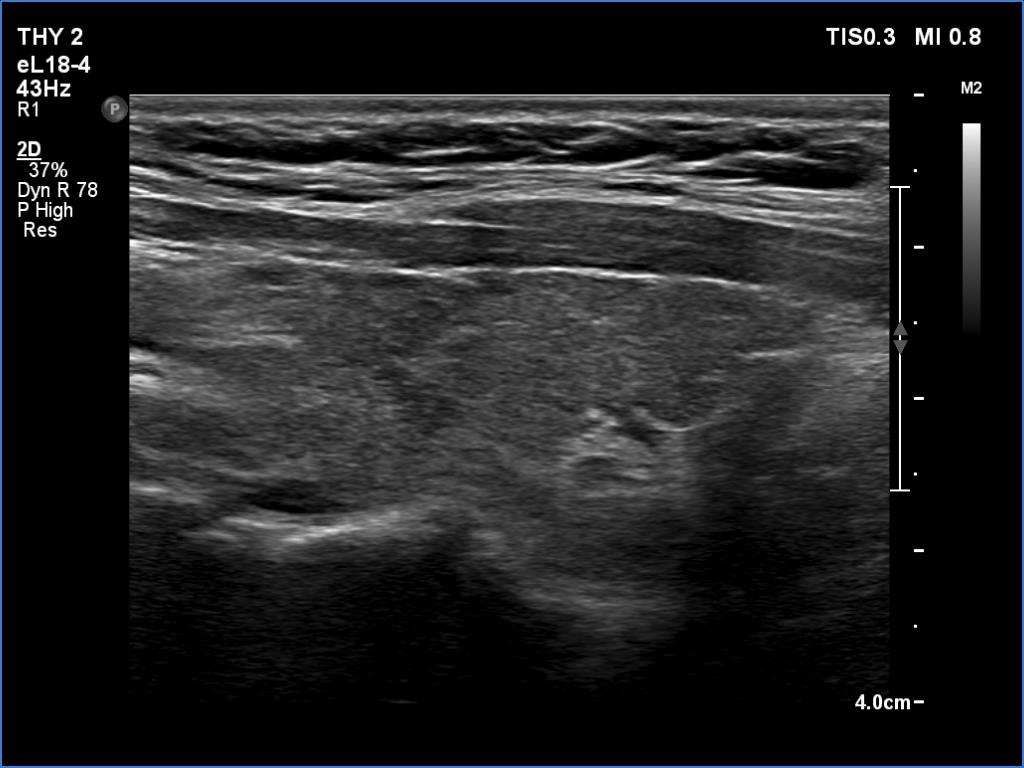

Lymphocytic thyroiditis - case 188

Follow-up investigation 2 years after the first visit (ultrasonographic picture 2)

Right lobe, longitudinal scan. There are several more hypoechoic areas.